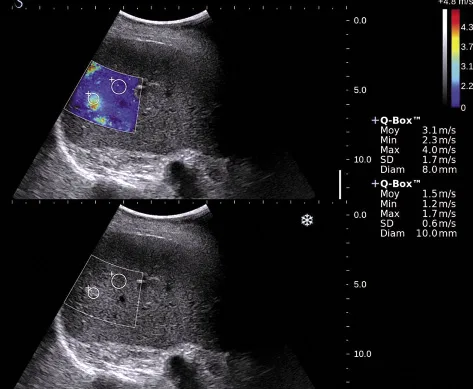

Figure 3. Écran de mesure de la dureté hépatique avec la technique SSI. Tous les pixels d’un cadre donné ont une valeur de dureté. On obtient ainsi une carte paramétrique de la dureté tissulaire. Une valeur quantitative moyenne peut être obtenue dans un ROI (region of interest). La valeur est donnée en m/s ou en KPa.